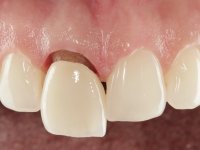

The patient came to the consultation because she did not like the “dark line next to the gums” that she had on her upper right central incisor.

Female patient, 33 years old, non-smoker. Tooth 11 with endodontic treatment rehabilitated with a crown. This crown shows an infiltrated cervical interface. The smile line was high, this area being very visible. The patient had a thick gingival phenotype and good oral hygiene.